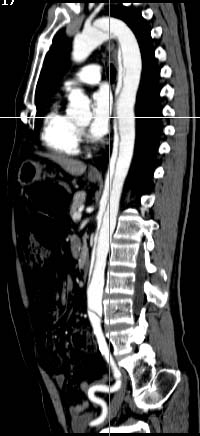

MPR

Data acquired & processed by H. Anno M.D.

Copyright (c) 1999 by Fujita Health University. All rights reserved